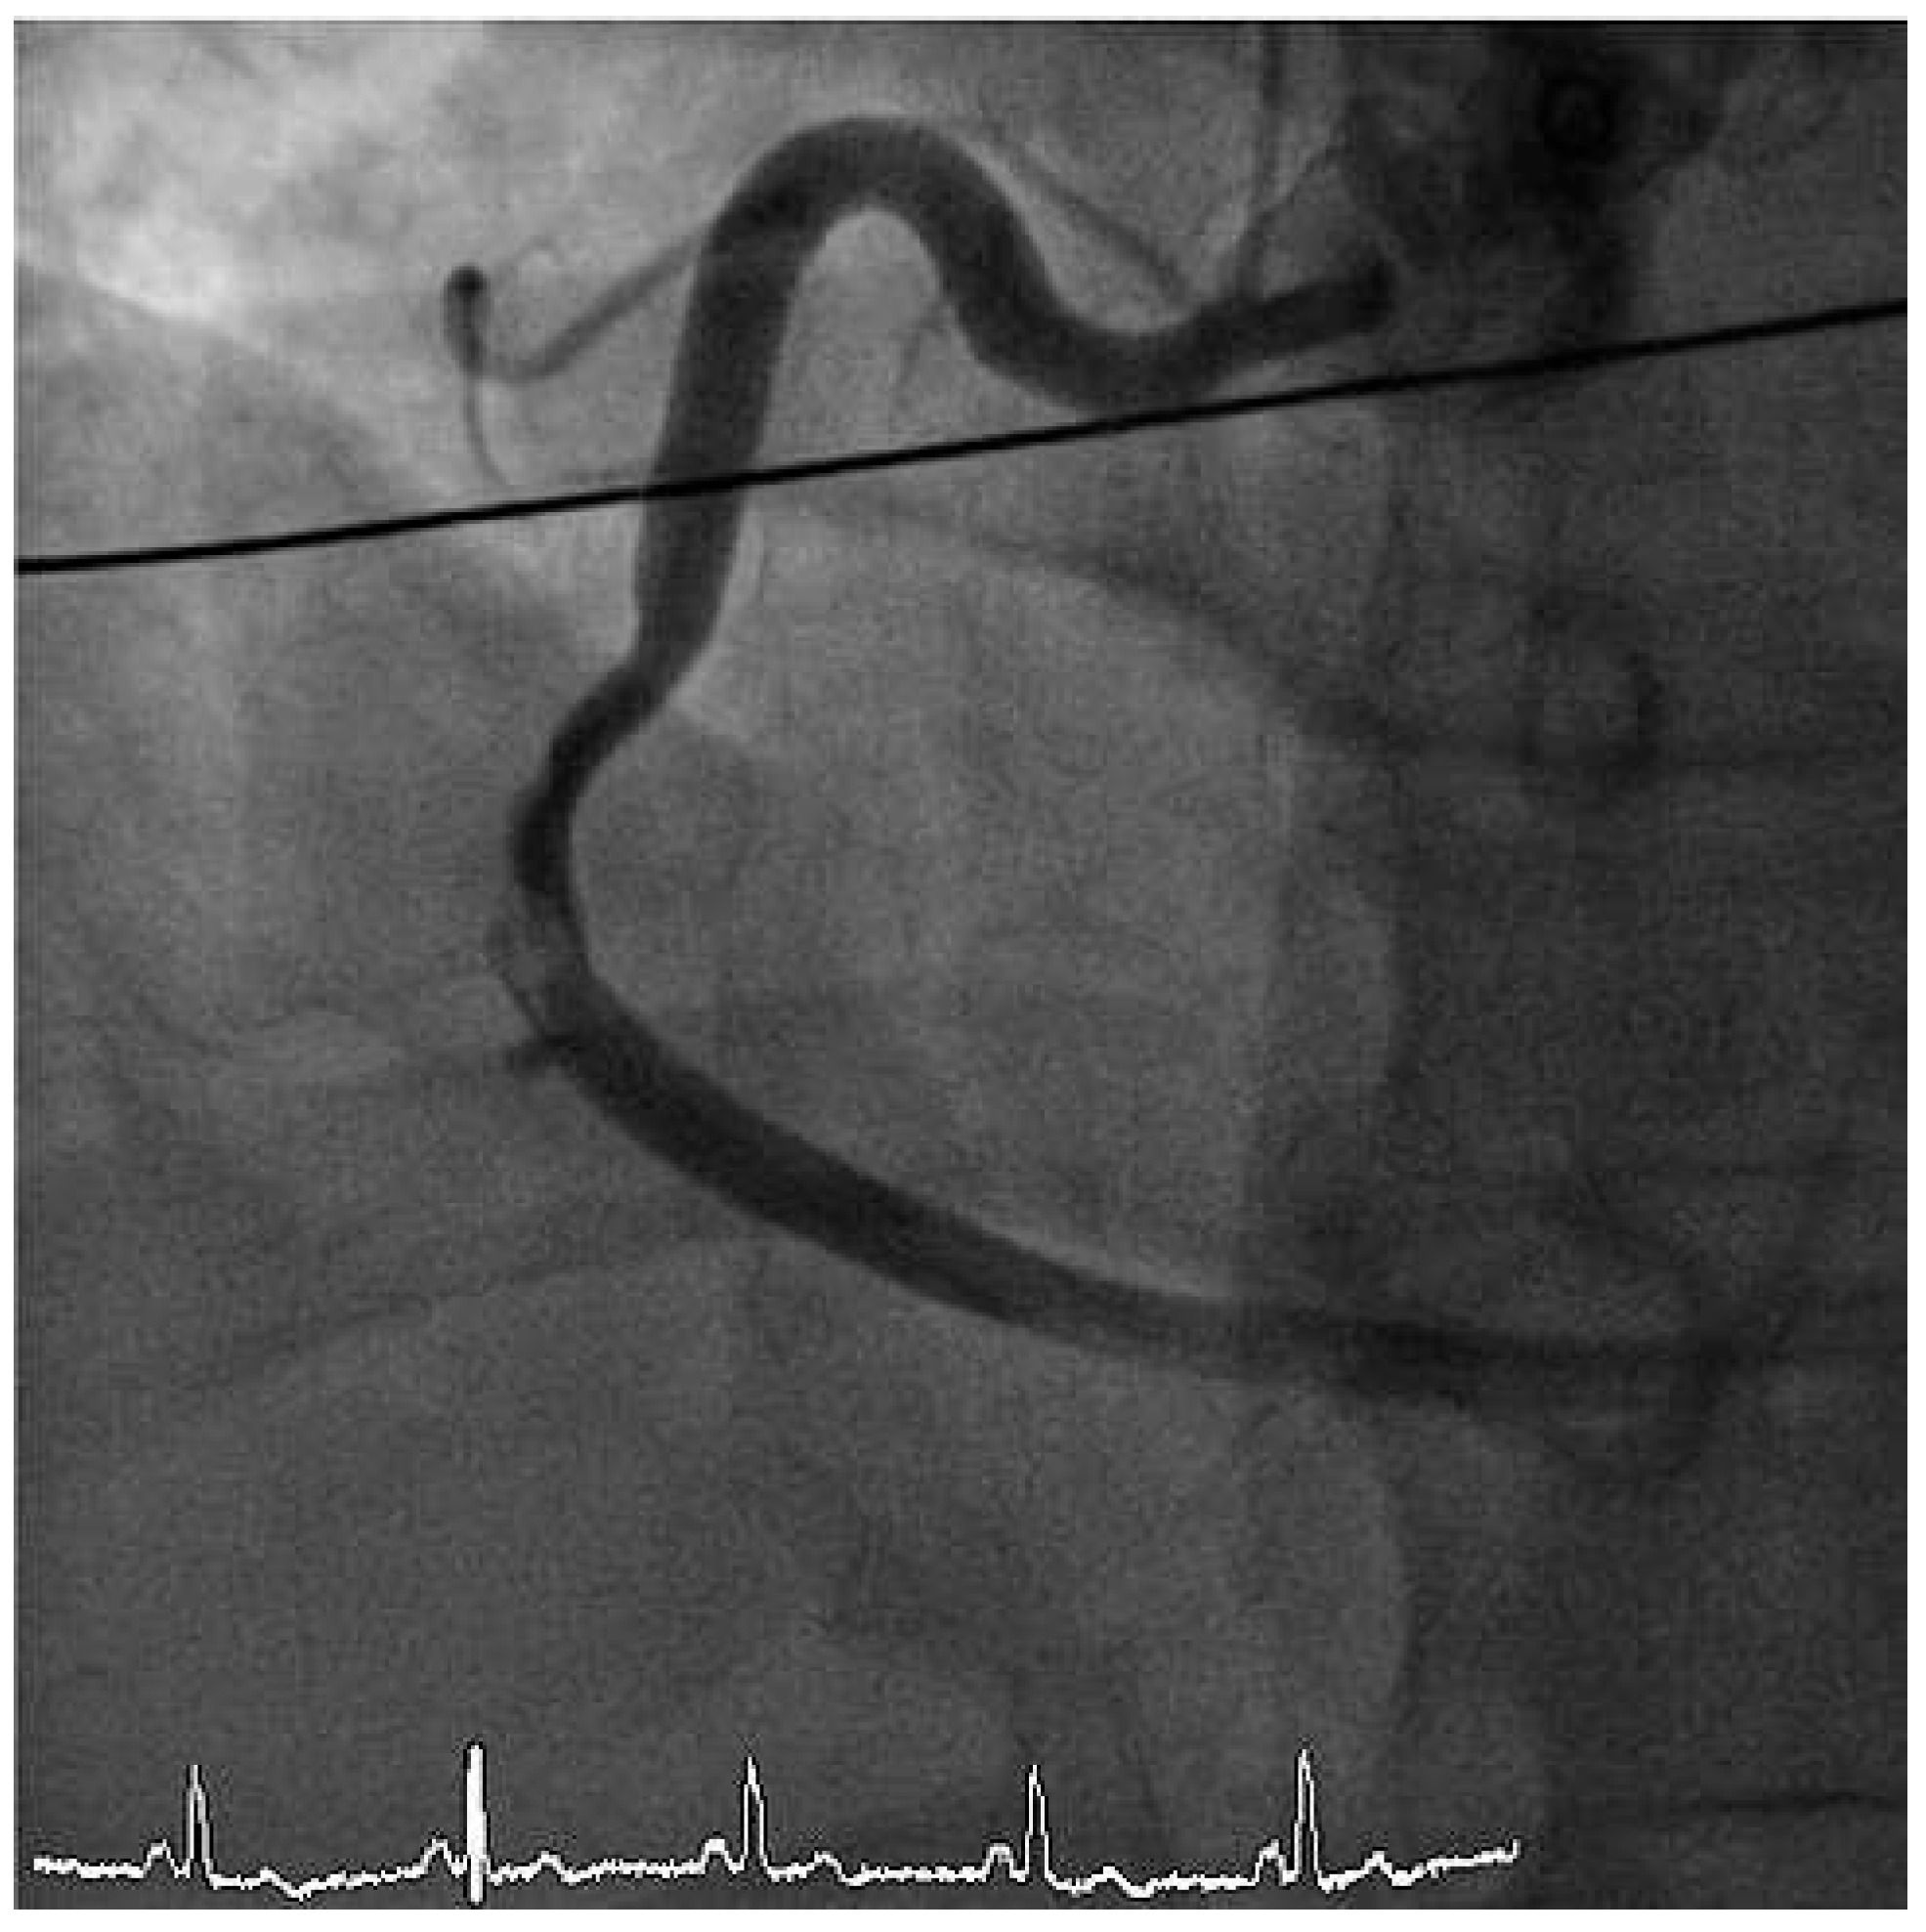

The ECG at admission showed normal sinus rhythm and ST-segment changes in the infero-lateral and the antero-septal leads (Figure 1). The initial troponin and CK-values were normal. Clinically the patient was in cardiogenic shock. Urgent invasive assessment revealed a severely depressed LV-function (EF 30%) with apical, anteroseptal and posterolateral akinesia. There was a total thrombotic occlusion of the mid LAD and the distal circumflex artery (Figure 2).

Figure 3. LAO cranial view showing right coronary artery with subtotal thrombotic occlusion.